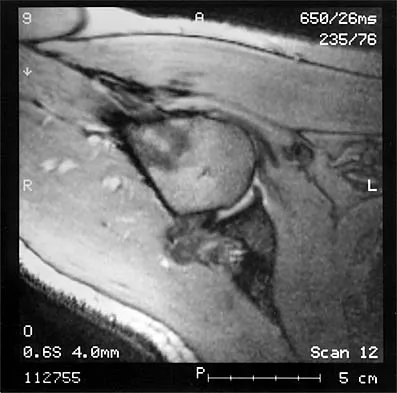

A 32-year-old woman has had pain and a visibly growing mass in the shoulder for 3 years but denies any history of trauma. Examination reveals a swollen, boggy shoulder mass. The AP radiograph and MRI scan are shown in Figures 20a and 20b. Figures 20c through 20e show a portion of the excised mass and the photomicrographs of the biopsy specimen. What is the most likely diagnosis?

Explanation